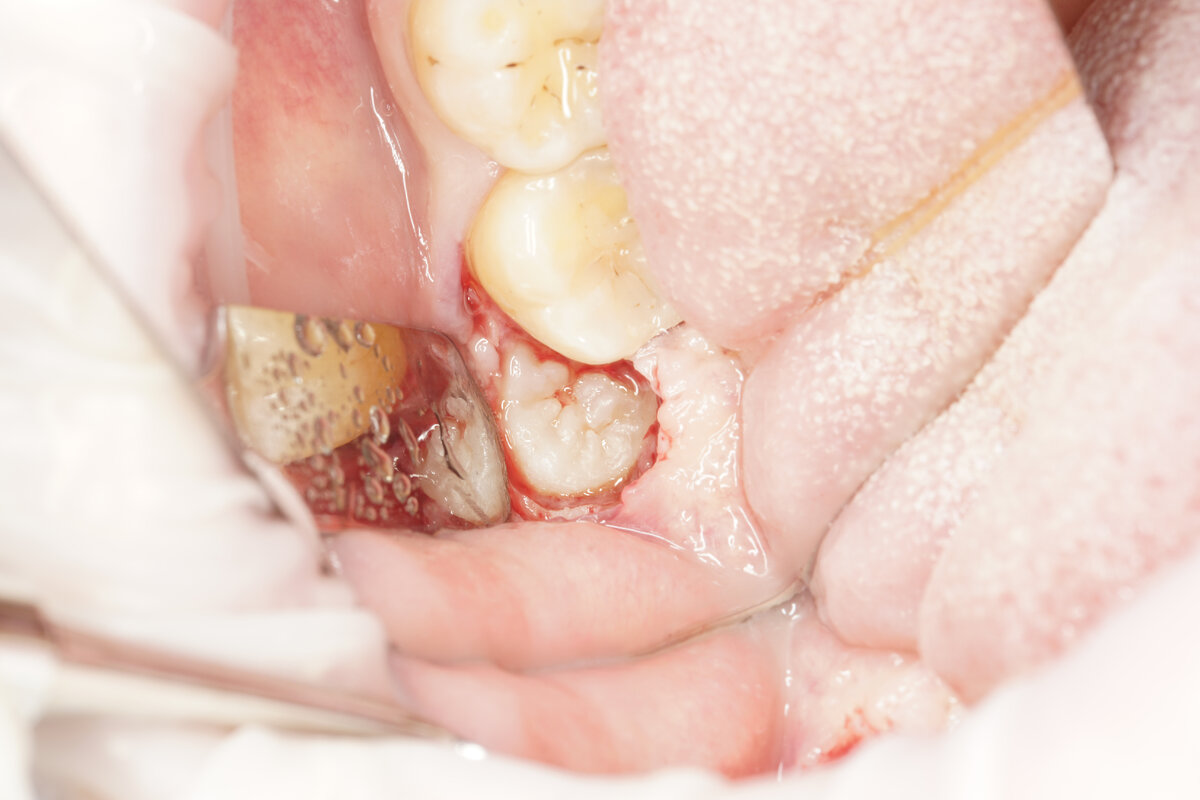

Само удаление занимает от 15 до 75 минут. Длительность процедуры зависит от анатомии зуба и его положения в челюсти. Не последнюю роль играют и мануальные навыки хирурга. Больше времени уйдет на удаление ретинированных зубов, полностью находящихся в кости. Будьте готовы, что доктор воспользуется бормашиной – с ее помощью он сможет фрагментировать зуб и удалить его атравматично, то есть с минимальным риском для окружающих тканей.

После удаления зуба в лунке формируется кровяной сгусток, а поверх ее накладываются швы. Привкус крови во рту и содержание крови в слюне не должны пугать – это норма. Насторожить должно лишь быстрое наполнение ротовой полости кровью.